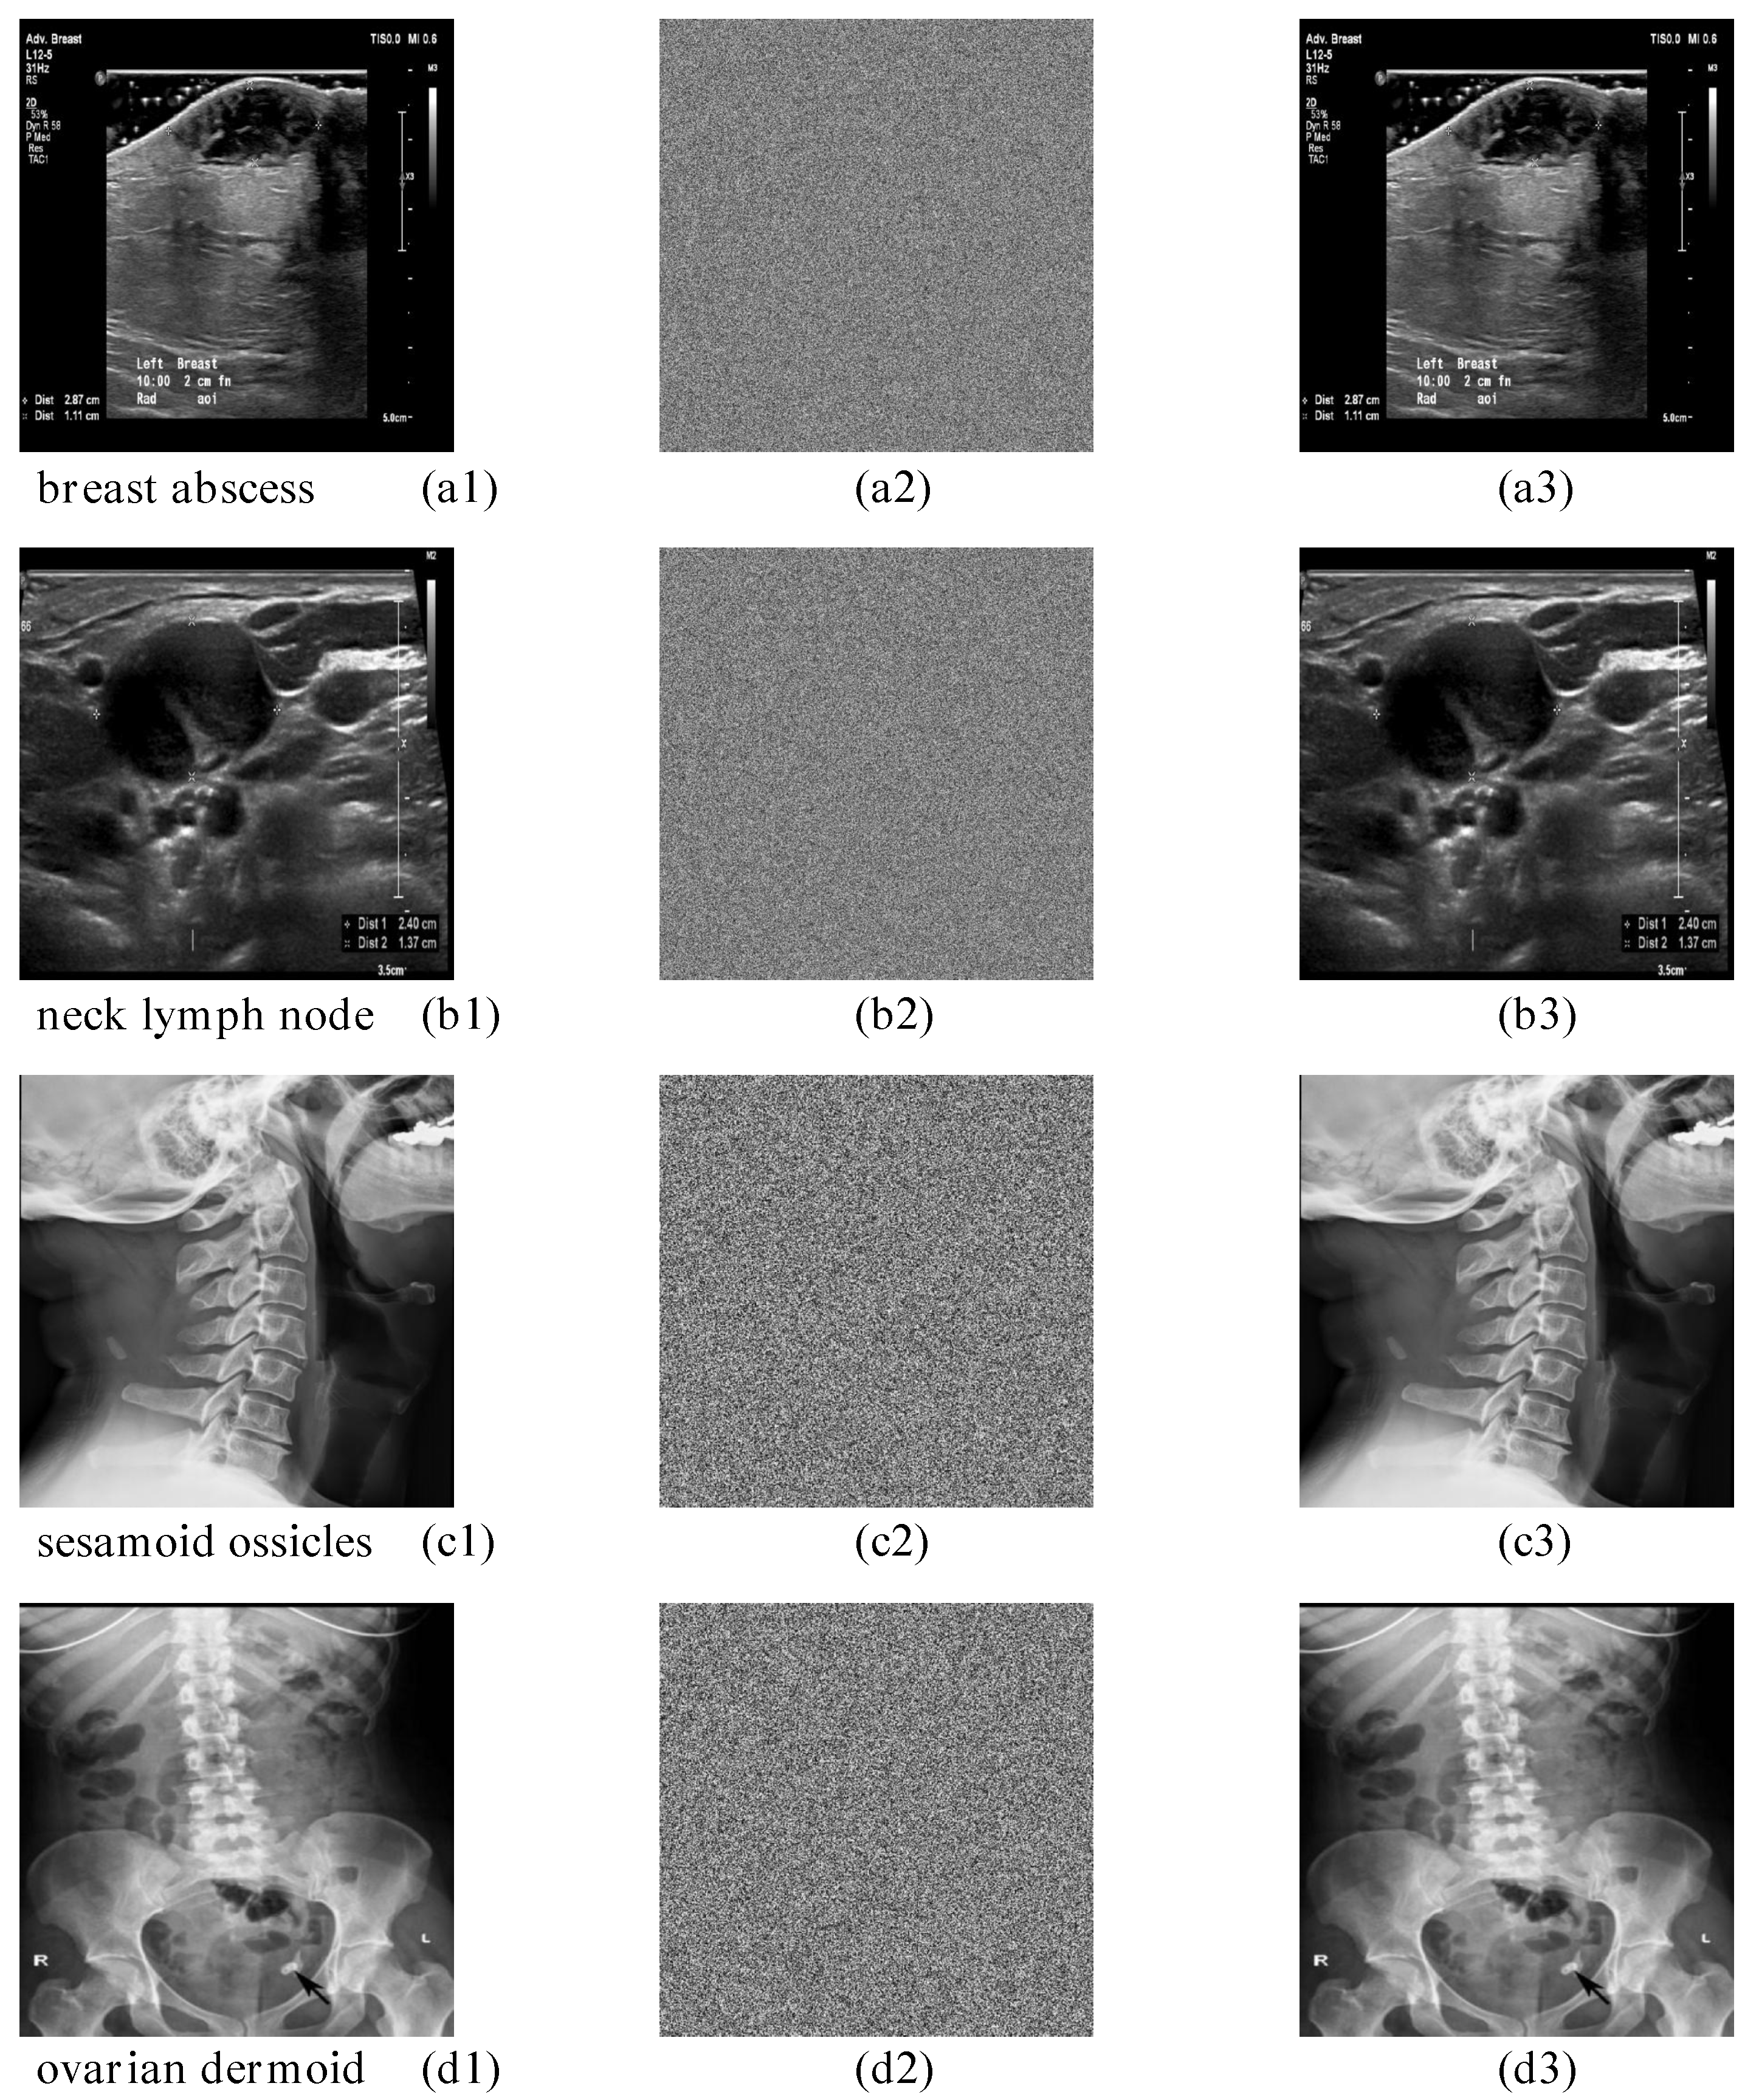

| neck lymph node (1024 × 1024) | 99.6146% | 33.5104% | pass |

| breast abscess | 99.6067% | 33.4941% | pass |

| sesamoid ossicles (512 × 512) | 99.6029% | 33.4897% | pass |

| ovarian dermoid | 99.6010% | 33.5327% | pass |